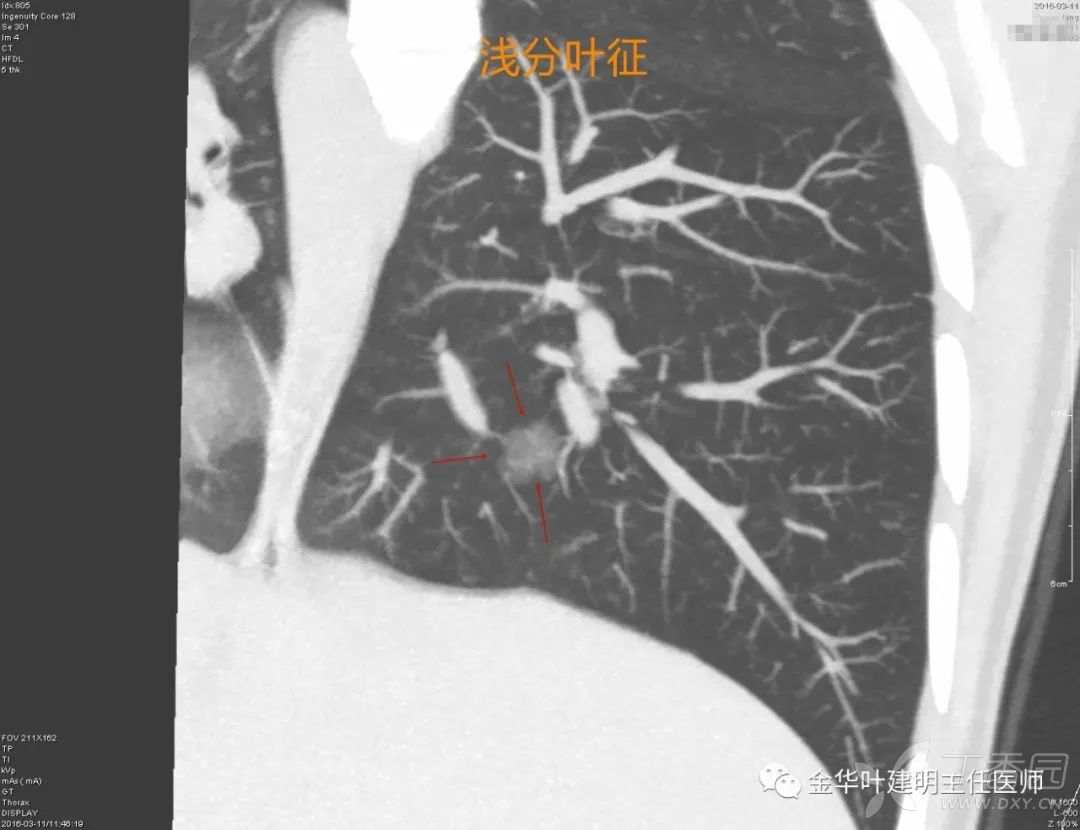

浅分叶征

浅分叶征:病灶表面凹凸不平,略不平则是浅分叶,因为肺小结多整体并不大,所以往往是浅分叶而已。形状像土豆。上图中红色箭头所指就是稍微凹点进去的地方。